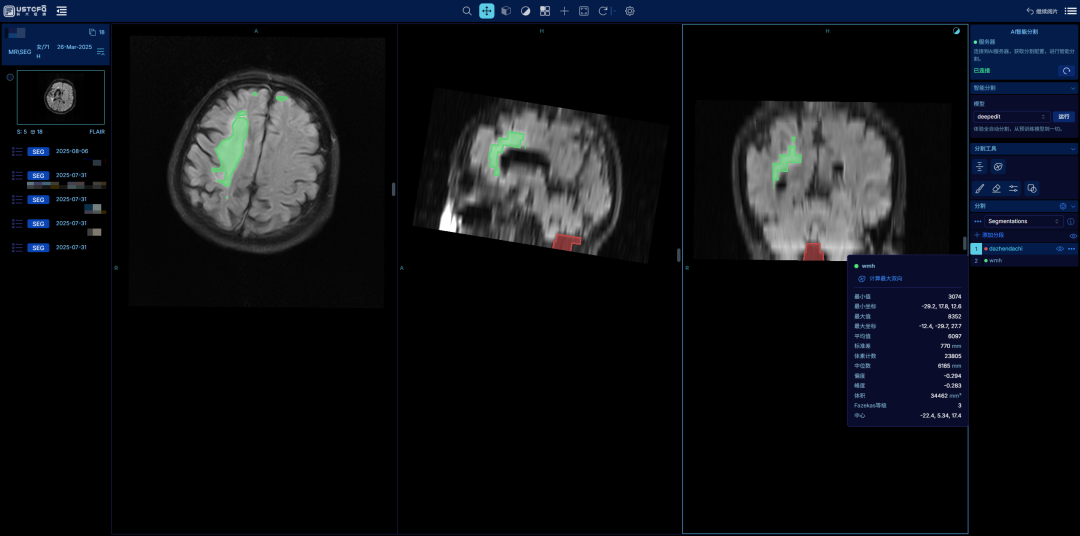

1、 用户可以使用预训练的模型直接标记大枕大池区域和脑白质区域,并查看相关区域的参数。

2、用户通过分割工具对颅脑标记的区域进行微调,或者添加不同的分段。